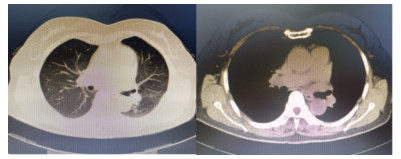

患者,女,64岁,居住农村,既往有糖耐量异常5年,未正规治疗,4年前诊断为“原发性甲状腺功能亢进”,经治疗已好转。无高风险、中风险地区旅居史,无境外旅居史,无新冠病毒肺炎确诊或疑似患者接触史。2020年7月31日患者无明显诱因下在家中出现发热,体温最高39.4 ℃,伴畏寒、全身乏力,无胸闷、胸痛,无咳嗽、咳痰,无腹痛、腹泻,无黑矇、晕厥,遂在家中自服“退热药”后体温降至正常,但体温仍有反复。8月2日早晨患者再次出现发热,伴畏寒、寒战,遂至本院发热门诊就诊,予查C-反应蛋白156 mg/L,降钙素原0.64 ng/L,考虑感染性发热,遂予“哌拉西林他唑巴坦钠4.5 g每12 h一次”静滴抗感染治疗,后患者突发呼吸费力,伴咳嗽、咯血,为鲜红色血液,量较多,遂于8月2日14:18送达本院急诊抢救室。来时患者呼吸急促,有咳嗽伴咳血性痰,双侧小腿持续性钝痛,查体:血压188/86 mmHg(1 mmHg=0.133 kPa),心率168次/min,呼吸36次/min,血氧饱和度50%,体温38.6 ℃。神志清,精神软,急性面容,双侧结膜略充血,全身皮肤黏膜未见明显充血、淤血,未触及淋巴结肿大。口唇微绀,两肺呼吸音粗,可闻及明显湿性啰音,心律齐,无明显病理性杂音;腹平软,无压痛反跳痛,四肢肌力Ⅴ级,两侧病理征未引出。予心电监护、特级护理、面罩吸氧、建立静脉通道,送检血常规、生化、血气、心肌酶、凝血酶原时间系列、痰培养等常规检查,同时予送检血标本行高通量测序,完善胸部CT检查(图 1)。辅助检查结果如下:8月2日胸腹部CT示两肺感染,腹部未见明显异常。血常规:白细胞计数7.9×109/L,中性粒细胞百分比89%,血红蛋白121 g/L,血小板计数104×109/L,C-反应蛋白156.82 mg/L。血生化:丙氨酸氨基转移酶51 U/L,天门冬氨酸氨基转移酶63 U/L,白蛋白34.5 g/L,总胆红素17.4 mmol/L,肌酐74 mol/L。心肌酶谱:心肌肌钙蛋白I 0.014 ng/mL,肌红蛋白322 ng/mL,肌酸激酶同工酶3.2 ng/mL。血气分析:pH 7.435,二氧化碳分压29 mmHg,氧分压53.5 mmHg,K+ 2.6 mmol/L,Na+ 132 mmol/L,血乳酸3.1 mmol/L。新型冠状病毒抗体、核酸阴性。接诊医师初步诊断为“咯血待查:疑似肺部感染,呼吸衰竭”,治疗上予亚胺培南0.5 g静滴经验性抗感染、甲泼尼龙80 mg静滴抗炎,同时予化痰、平喘等对症、支持。17:00患者出现呼吸费力加重,10 L/min面罩吸氧下血氧饱和度仍为70%,故予紧急气管插管、机械通气,随后转入ICU,联系感染科医师会诊,结合患者病史及CT影像学表现的广泛、片状密度增高影特点,考虑钩端螺旋体病可能性大,不排除“赫氏反应”,故继续予亚胺培南0.5 g静滴每6 h一次抗感染、甲泼尼龙80 mg静滴每12 h一次抗炎、白蛋白营养支持等治疗。8月3日更改甲泼尼龙80 mg静滴每天一次。8月4日高通基因测序回报:检测出问号钩端螺旋体DNA,符合入院时推断,明确病原体后予修正诊断为肺出血型钩体病伴赫氏反应。8月5日停亚胺培南,改青霉素160万单位静滴每8 h一次。8月8日患者病情稳定,拔除气管导管,予甲泼尼龙减量为40 mg静滴1次/d,8月9日复查胸部CT提示两肺斑片状、片状密度增高影较前有所吸收(图 2),停用甲泼尼龙。8月10日转入呼吸科。8月17日复查胸部CT提示两肺斑片状、片状、条索状密度增高影,较前明显吸收(图 3)。8月20日患者好转出院。9月18日随访,复查CT提示两肺散在条索状密度增高影,基本恢复正常(图 4)。

图 1 8月2日入院时胸部CT呈弥漫性密度增高影